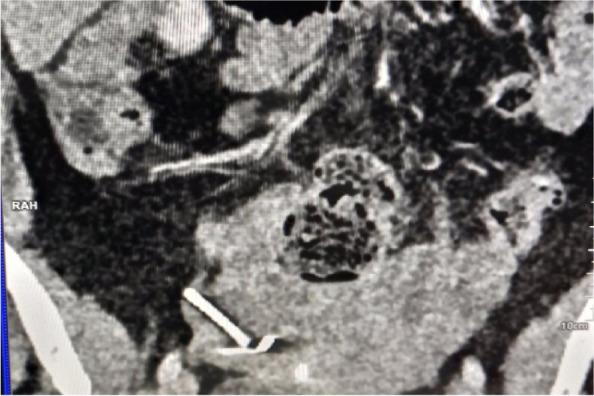

Loss of Intra Uterine Device (IUD) following silent perforation of the uterus either during or after IUD insertion is an uncommon finding due to a lack of immediate follow-up. We report a rare case in which uterine perforation following the migration of IUD to the right fallopian tube without visceral injury. The patient presented with lower abdominal pain and pain during sex for one year since IUD insertion. On examination, we noted tenderness on the right suprapubic region and on speculum examination, no IUD thread was seen. A radiological pelvic examination showed an empty uterus without an IUD. Laparotomy and retrieval of migrated IUD was done followed by repair of perforated uterus.

宫内节育器(IUD)在插入过程中或插入后因子宫隐性穿孔而丢失,由于缺乏即时随访,这种情况并不常见。我们报告一例罕见病例,宫内节育器迁移至右侧输卵管后发生子宫穿孔,但无内脏损伤。该患者自放置宫内节育器后出现下腹部疼痛和性交痛一年。检查时,我们发现耻骨上区右侧有压痛,阴道窥器检查未见宫内节育器尾丝。盆腔放射学检查显示子宫内无宫内节育器。进行了剖腹手术并取出迁移的宫内节育器,随后修复穿孔的子宫。